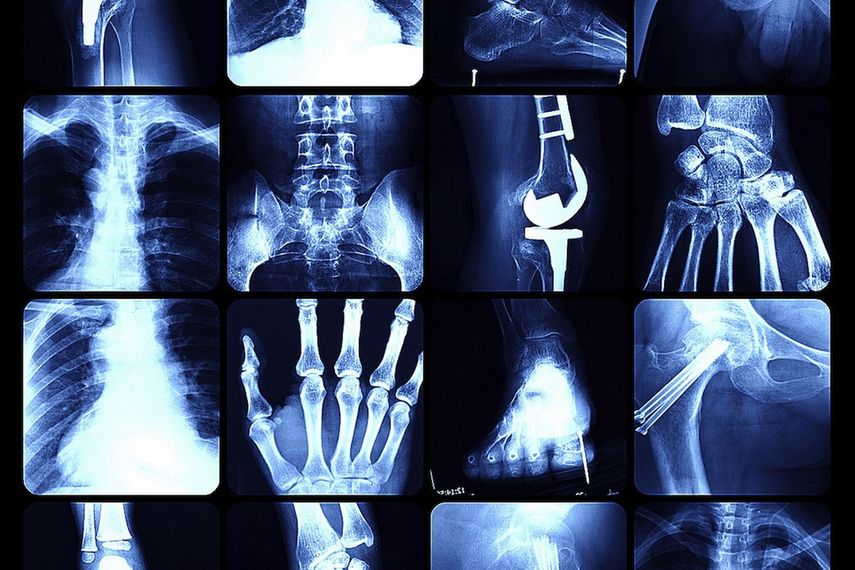

Osteoporosis

Cuando los huesos son de cristal

La osteoporosis, es una patología silenciosa que afecta a los huesos, y es provocada por la disminución, tanto del tejido que los conforma, como de las proteínas contenidas en su estructura. Al debilitarse el esqueleto, aumenta la posibilidad de fracturas, pero como se trata de una enfermedad asintomática, pocos están conscientes de padecerla. n

El hueso: es un tejido vivo que se encuentra en constante estado de regeneración, es decir, nuestro cuerpo tiene la capacidad de eliminar los viejos, en un proceso llamado resorción ósea, y de reemplazarlos con nuevas formaciones. A partir de los 35 años, la mayoría de las personas comienzan a perder densidad en la estructura esquelética, haciendo que nuestra estructura interior se vuelva más delgada y frágil.